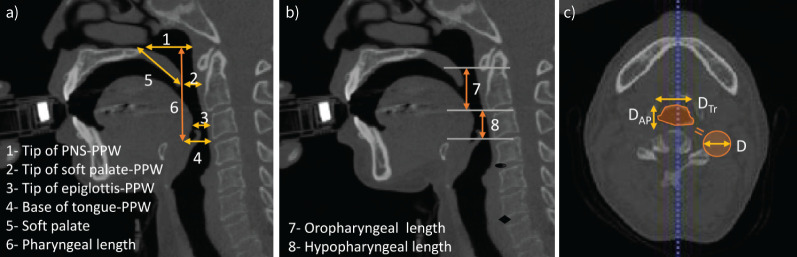

背景:虽然对哮喘、COPD等阻塞性肺疾病(OLDs)的下气道重构进行了全面的研究,但对OLD的上气道重构的了解仍然有限。本研究旨在利用定量计算机断层扫描(QCT)成像研究OLD患者的上呼吸道尺寸,并利用机器学习技术确定预测OLD的相关参数。方法:对26名健康对照者、73名COPD患者和86名哮喘患者进行了从口腔到声门下区域的上呼吸道计算机断层扫描(CT)。使用ITK-SNAP和内部QCT软件评估多尺度肺结构和功能。利用streamlined的特征重要性估计方法来选择可能相关的上呼吸道指标。两两比较采用Wilcoxon秩和检验,相关分析采用Pearson相关检验。使用约登指数确定相关上呼吸道特征的最佳截断值。结果:在标准化QCT结果后,OLD患者表现出更大的口到声门上指标,特别是更大的口腔空间空气分数和咽部长度。两项指标均与1 s内用力呼气量/用力肺活量呈负相关(R=-0.24; p=0.001)。特征重要性分析确定口腔空间空气分数和正常咽部长度是区分老年痴呆症患者和健康对照者的关键特征。口腔空气分数≥0.8预测老年痴呆的敏感性约为100%,特异性约为69%。结论:上呼吸道CT定量测量结合机器学习分析可显示老年患者口咽肿大。

Methods: A prospective cohort of 26 healthy controls, 73 COPD patients and 86 asthma patients underwent upper airway computed tomography (CT) scans from the oral cavity to the subglottal region. Multiscale lung structure and function were assessed using ITK-SNAP and in-house QCT software. Feature-importance estimation methods from STREAMLINE were utilised to select potentially relevant upper airway metrics. The Wilcoxon rank-sum test and Pearson's correlation were employed for pairwise comparisons and correlation analysis, respectively. The Youden index was used to determine optimal cut-off values of relevant upper airway features.

Results: After standardising QCT results, patients with OLD exhibited greater mouth-to-supraglottal metrics, notably greater oral space air fraction and pharyngeal length. Both metrics showed a negative correlation with forced expiratory volume in 1 s/forced vital capacity (R=-0.24; p=0.001). Feature-importance analysis identified oral space air fraction and normalised pharyngeal length as key features discriminating patients with OLD from healthy controls. An oral space air fraction value of ≥0.8 predicted OLD with approximately 100% sensitivity and 69% specificity.